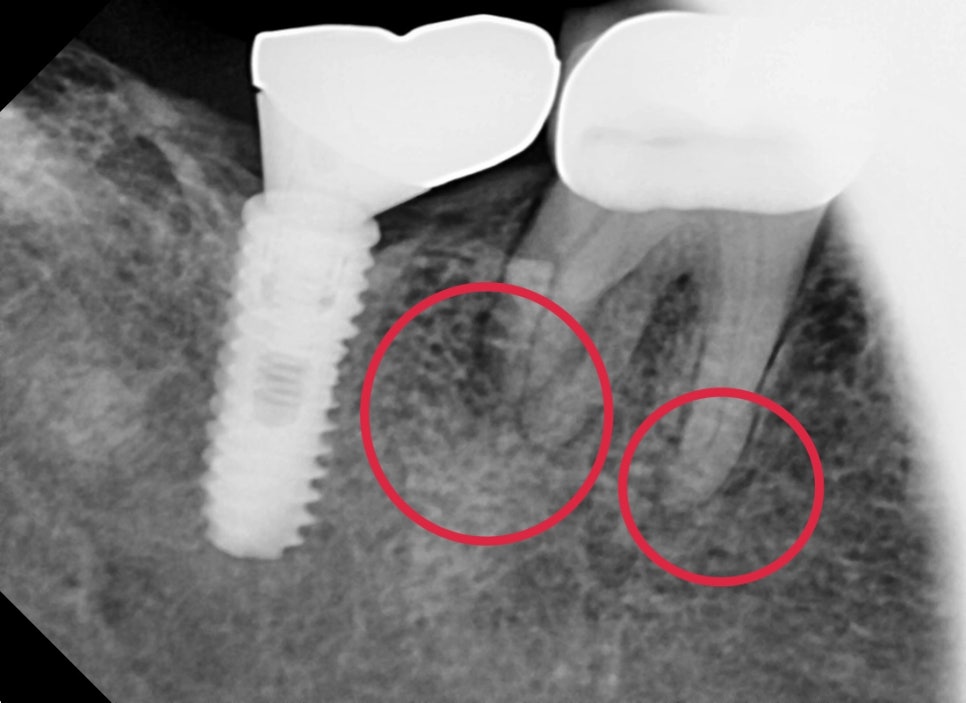

자세하게 확인하기 위해 해당 치아만 따로 엑스레이 촬영을 했습니다

어금니 뿌리가 4개가 있는데 모두 뿌리 쪽의 염증이 확인되었습니다.

통증이 있던 이유는 염증이 생기면서 압력이 생겨 불편감을 호소하시는 중이었습니다.

보통 이런 케이스는 자극이 지속적으로 치아에 가해지면서

치아는 스스로를 보호하기 위해 신경관이 좁아지는 석회화 반응으로

신경관 입구를 찾기가 까다로운 경우가 있습니다.

신경치료가 끝난 직후의 엑스레이 사진입니다.

염증이 심했던 치아는 뿌리끝 쪽이 신경관을 밀봉하는 재료가

화살표와 같이 뿌리끝까지 밀려나오며 바깥쪽까지 밀봉해 주는 경우가 있습니다.

물론 해당 재료는 생체친화적이기 때문에 추후 일부는 흡수가 되기도 합니다.